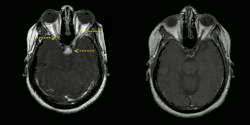

Right image: MRI brain with contrast showing near resolution of enhancement after treatment.

MRI with gadolinium enhancement is the most useful neuroimaging test. This may show enhancement of the pia mater or white matter lesions that may resemble the lesions seen in multiple sclerosis.[1]